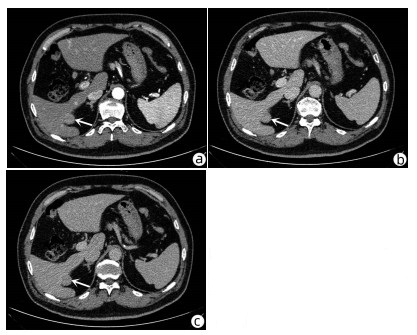

Heterotopic pancreas of the duodenum misdiagnosed as intraperitoneal tumor: A report of three cases

Xing LYU, Jianpeng ZHOU, Kai KOU, Xiaodong SUN, Guoyue LYU

2022, 38(3): 643-645. DOI: 10.3969/j.issn.1001-5256.2022.03.030

Abstract(760) HTML (351) PDF (3871KB)(58)

Abstract: